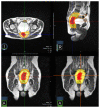

Materials and methods: For this prospective pilot study, patients diagnosed with locally advanced rectal cancer (LARC) with positive lymph node clinical staging underwent SMART on rectal lesion and mesorectum using hybrid MR-Linac (MRIdian ViewRay). Dose prescription at 80% isodose for the rectal lesion and mesorectum was 40 Gy (8 Gy/fr) and 25 Gy (5 Gy/fr), respectively, delivered on 5 days (3 fr/week). Response assessment by MRI was performed 3 weeks after SMART, then patients fit for surgery underwent total mesorectal excision. Primary endpoint was evaluation of adverse effect of radiotherapy. Secondary endpoint was pathological complete response rate. Early toxicity was graded according to the Common Terminology Criteria for Adverse Events (CTCAE v5.0).